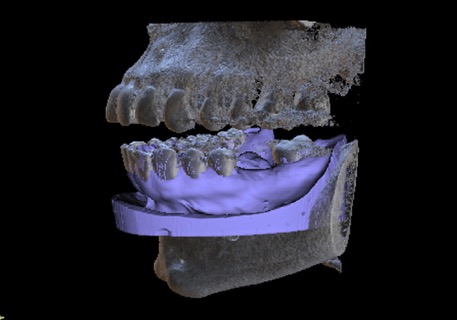

1. CBCT and model merge

Supply a CBCT of the patient and a PVS impression or intra oral scan. We will accurately merge the model with the CBCT so the guide can be made to fit accurately and be tooth and if need be tissue supported. This is a special feature that allows us to offer perfectly fitting guides. Edentulous solutions are also available including tissue or bone supported guides.

Various types of guides are available for you to select. All can be tooth borne, tissue borne bone supported* or a combination of each. * Bone supported guides are dependant on CBCT quality.